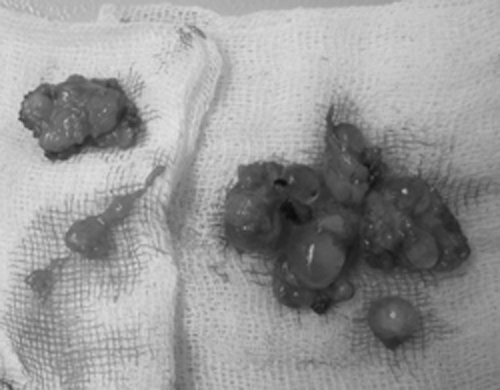

Các khối silicon bị vón cục lấy ra từ ngực bệnh nhân. Ảnh: Thiên Chương

Bác sĩ Nguyễn Văn Việt Hảo, Giám đốc trung tâm thẩm mỹ Hàn Quốc, cho biết silicon lỏng đă gây biến chứng. Thay v́ tụ thành khối, các mảng silicon đă tách rời ra.

"Để ngực bệnh nhân không bị xâm lấn, chúng tôi đă phẫu thuật loại bỏ silicon. Rất nhiều vón cục silicon dạng quả trứng được lấy ra. Tuy nhiên, việc nạo vét silicon vẫn không thể trọn vẹn v́ có thê ảnh hưởng đến mô ngực", ông Hảo cho hay.